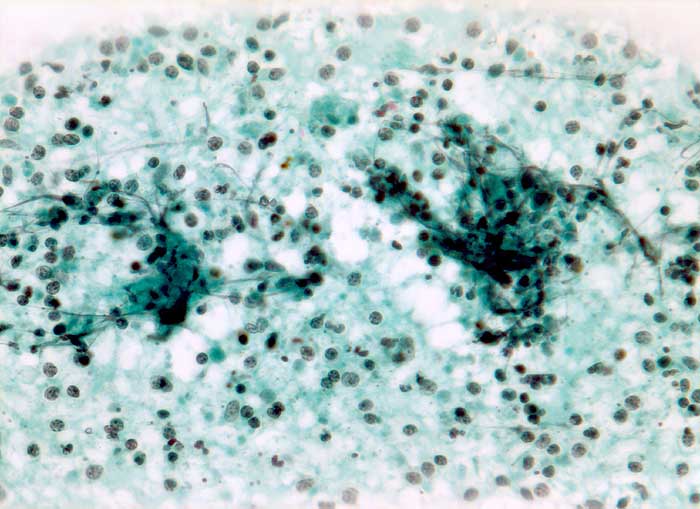

Tuberkulose

Entzündung infektiös

Lymphknoten, Kopf-cervikal

Feinnadelpunktion Lymphknoten submandibulär: Die nicht sehr zellreichen Ausstriche enthalten Detritus vermischt mit neutrophilen Granulozyten und Kerntrümmern.

Fibrin (+) Blutbeimischung + Granulozyten + Lymphozyten (+) Histiozyten (+) Histiozytäre Riesenzellen (+) Plattenepithelien ++ Parakeratotische Plattenepithelien ++

Generalisierte Lymphadenopathie, Stomatitis, HIV positiv.

Zytologische Diagnose: Ausgeprägte granulozytäre Entzündung. Keine Malignitätszeichen.

320